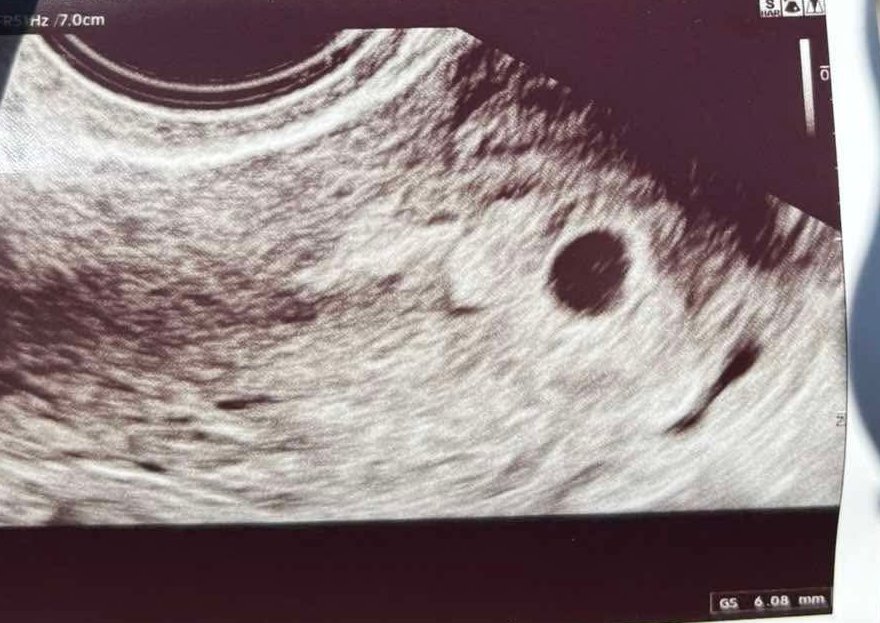

Здравейте,

За 5 г. с. как ви се вижда?Понеже не успя да се види нищо друго освен плоден сак

Selena2777,отговаря си за 4-5 г.с,няма как друго да се види на този етап.

След 10 дни ще се види и ембрион,успех!